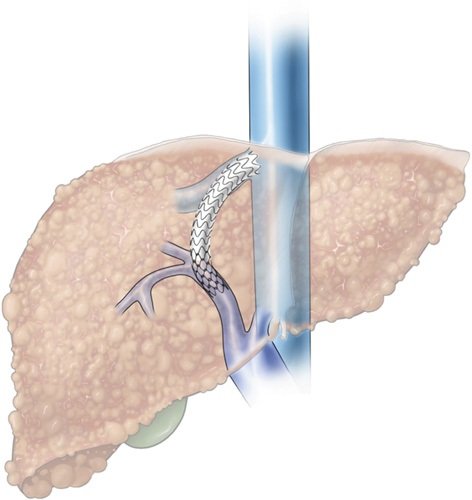

Life saving intervention..looking back 25 some years, couldn’t know in my wildest dreams that I would be able to, but I am fortunate & it has been a privilege to be able to offer it to patients in dire circumstances.

4 TIPS this week, 3/4 with moderate sedation, all under 30 mins to stent deployment. ICE and steerable needles are the future!